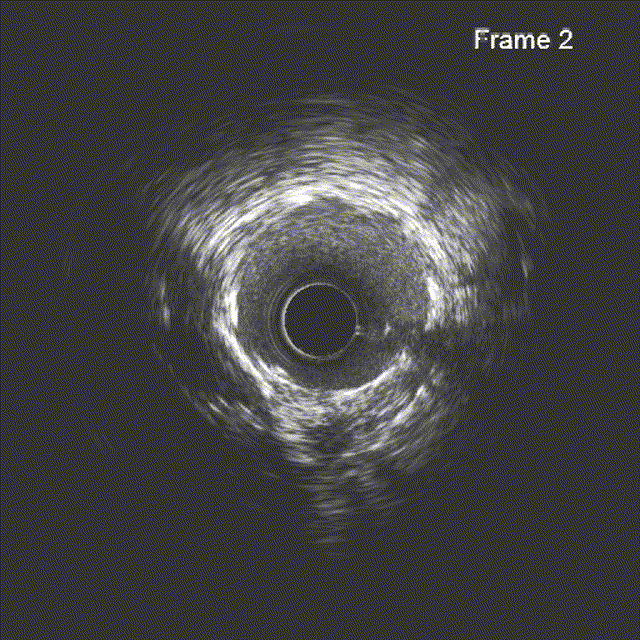

IVUS见左主干远段MLA:7.05mm²;前降支近段MLA:2.68mm²,中段MLA:2.63mm²,前降支近段至中段可见多发钙化小节突入管腔,局部90°-270°钙化,前降支开口至中段管腔直径约2.5-3.5mm,严重钙化段管腔直径约2.85-3.5mm。

根据IVUS结果,调整术式为精确定位前降支开口,预处理方式用3.0mm×12mm shockwave冠脉血管内冲击波导管。

冲击波导管送至左前降支,由中段至开口依次以4atm压力初始冲击扩张,6atm压力巩固扩张,共冲击扩张10秒×8个周期,可见球囊逐渐膨胀充分。此阶段在处理前降支开口时预置回旋支保护导丝。

复查IVUS提示前降支原近中段钙化斑块、钙化小节碎裂,未见明显夹层。